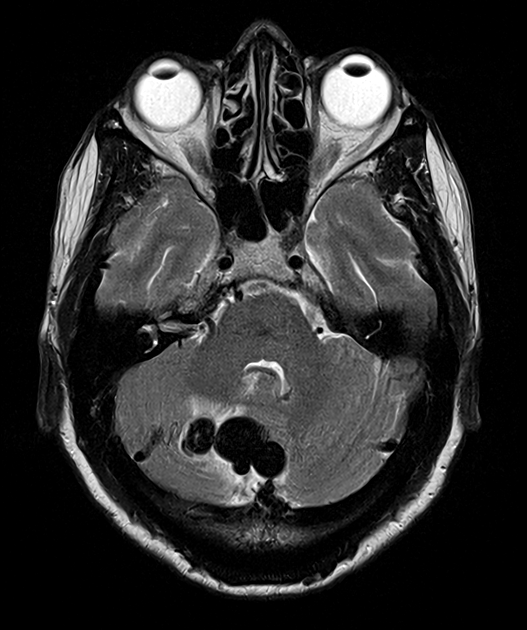

- A 60-year-old patient presented with headache.

- An MRI on admission showed a dilated vessel in the posterior fossa with a rim of oedema within the cerebellum.

- Immediately after the MRI, the patient's headache worsened and an CTA showed haemorrhage around the dural arteriovenous fistula that was supplied by the PICA.